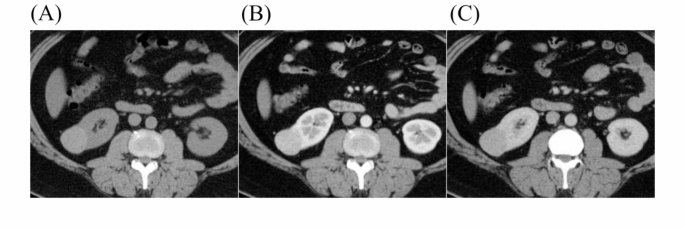

A 69-year-old man presented with a round, well-defined mass approximately 3.5 cm in diameter located in the lower pole of the left kidney. Another small non-enhancing cyst in the left kidney. On the unenhanced CT, the solid portion of the tumour appears slightly hyperdense (A). In the corticomedullary phase, the solid component of the tumour shows greater enhancement compared to the renal cortex (B, 3 points), with necrotic components of irregular morphology indicated (red arrow, 3 points). The enhancement in the nephrographic phase is reduced and lower than that in the renal cortex (C). The tumour exhibits a fast-in-fast-out enhancement pattern, with a pseudocapsule surrounding the tumour (yellow arrow, 2 points). The total score of 8 points in this case strongly suggested clear cell renal cell carcinoma, which was confirmed by the final pathological findings.